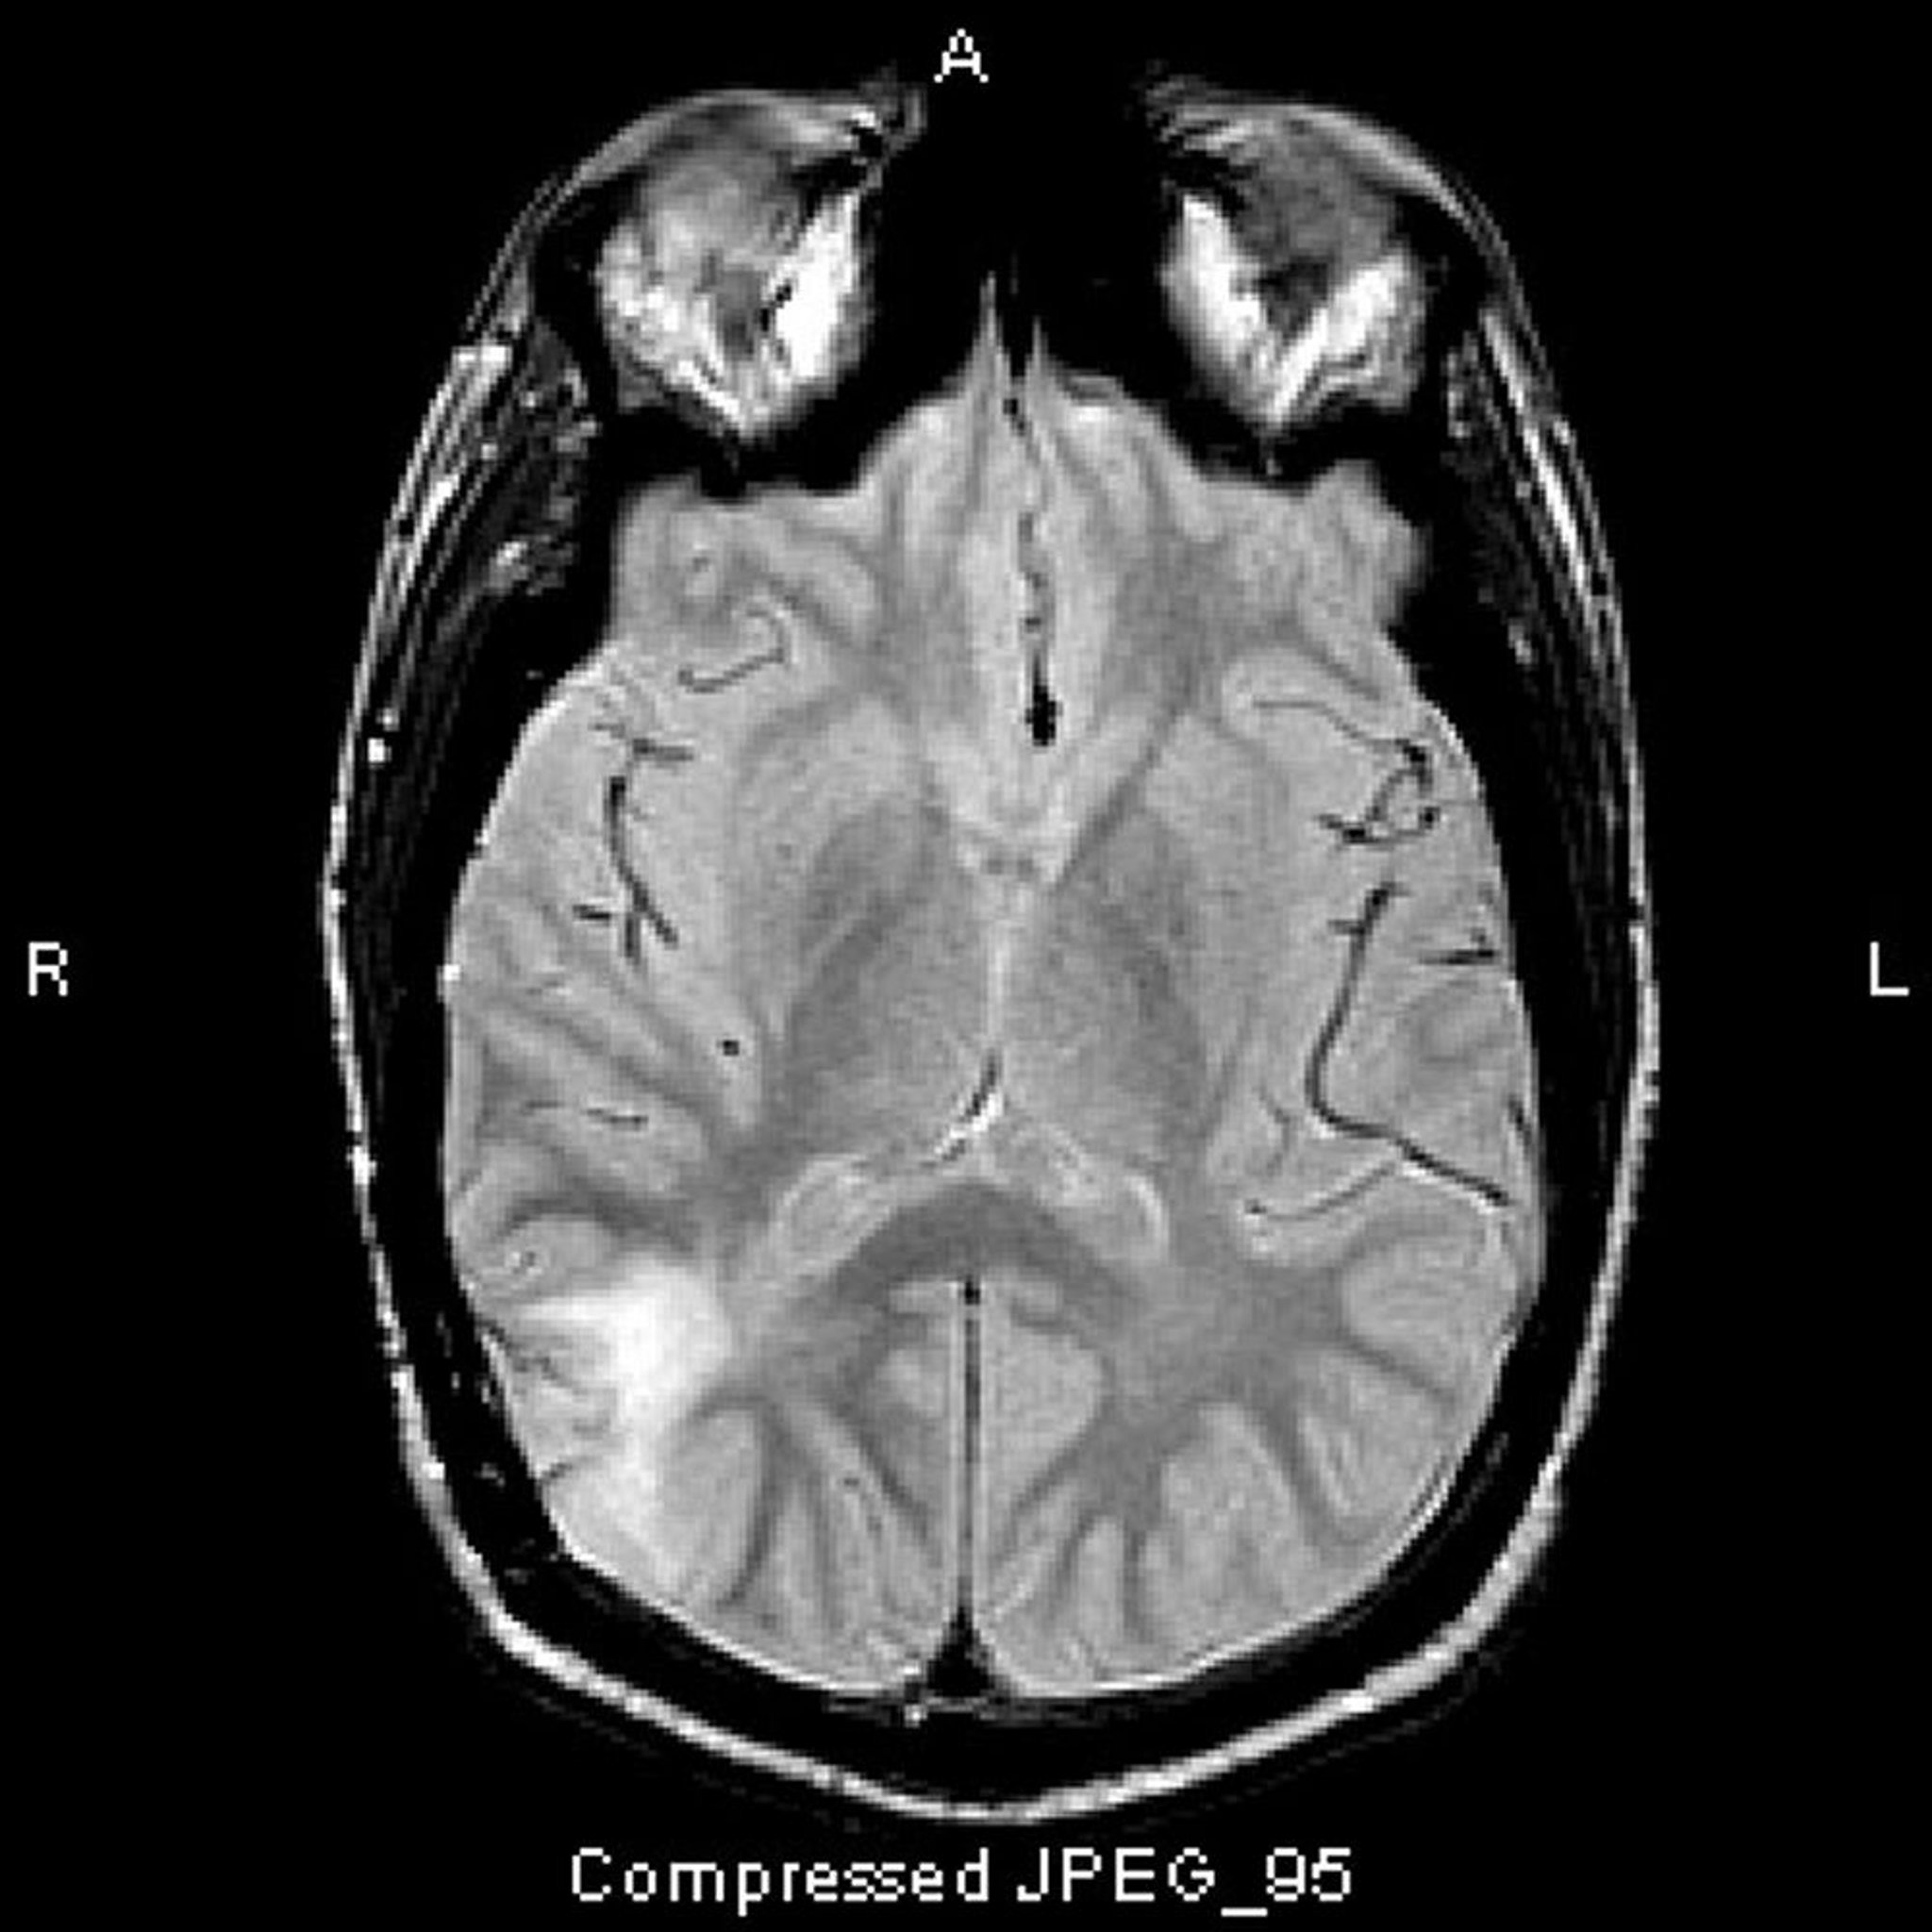

Astrocytome anaplasique

Cette IRM T2-FLAIR montre un signal blanc dans le lobe temporal postérieur. Le signal n'est pas augmenté par le contraste. C'est un astrocytome anaplasique (grade III).

Image courtoisie de William R. Shapiro, MD.